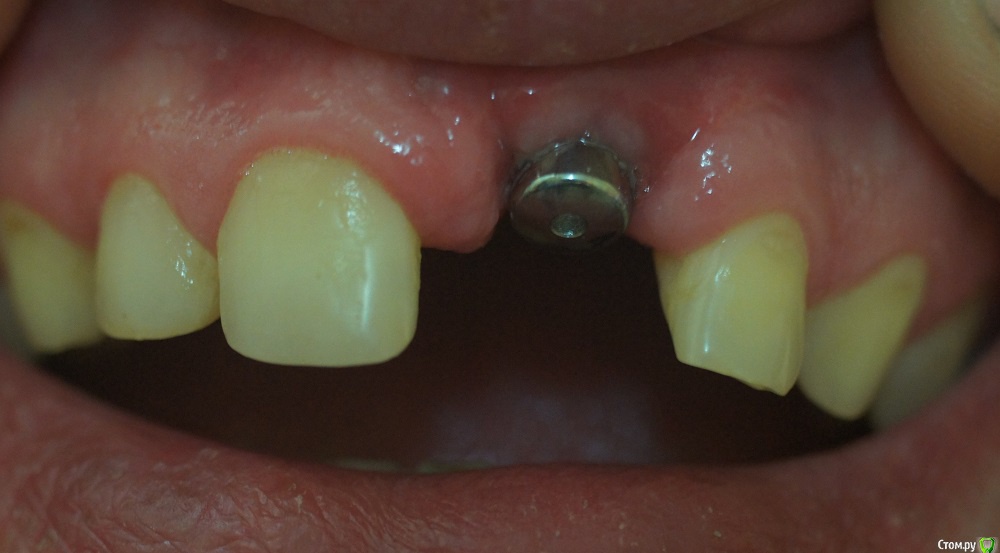

pekar Опубликовано 19 мая, 2016 Поделиться Опубликовано 19 мая, 2016 Здравствуйте. Поставили имплант (одномоментно с удалением больного зуба), а через 4 месяца формирователь, но десна ушла очень глубоко. Возможно ли это как то исправить? Изготовили зуб, мне он не понравился, очень длинный, бросается в глаза, хоть он и розового цвета в основании. Ссылка на комментарий

red_butler Опубликовано 23 мая, 2016 Поделиться Опубликовано 23 мая, 2016 Ситуацию можно улучшить с помощью пластики мягких тканей. 1 Ссылка на комментарий

Bier Опубликовано 23 мая, 2016 Поделиться Опубликовано 23 мая, 2016 можно улучшить, но коронку нужно выбросить. Нарастить десну, потом делать новую коронку 1 Ссылка на комментарий

Larnary Опубликовано 26 мая, 2016 Поделиться Опубликовано 26 мая, 2016 (изменено) Обращаться к хирургу. Он сделает пластику мягких тканей,а ортопед временной коронкой смоделирует десну и только потом уже постоянная коронка.Хирурга винить не буду,тк неизвестны условия до операции. Тут скорее несогласованность работы хирурга и ортопеда. Изменено 26 мая, 2016 пользователем Larnary Ссылка на комментарий